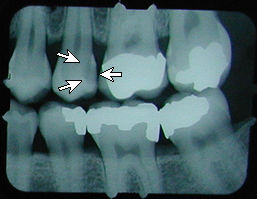

x-ray with cavity

No cavity on first X-ray.

Months later, cavities that start between the teeth can't be seen by visual examination, but they can be detected on an X-ray.

This cavity was detected and filled before the patient felt any discomfort, and before the nerve became infected or the tooth became abscessed.

There is another cavity shown in the X-ray on the right. Can you find it? It's difficult for the untrained eye to spot. Click here to see where it is. (Hint: It's not the left edge of the top left tooth. That's just the edge of the frame around the X-ray).